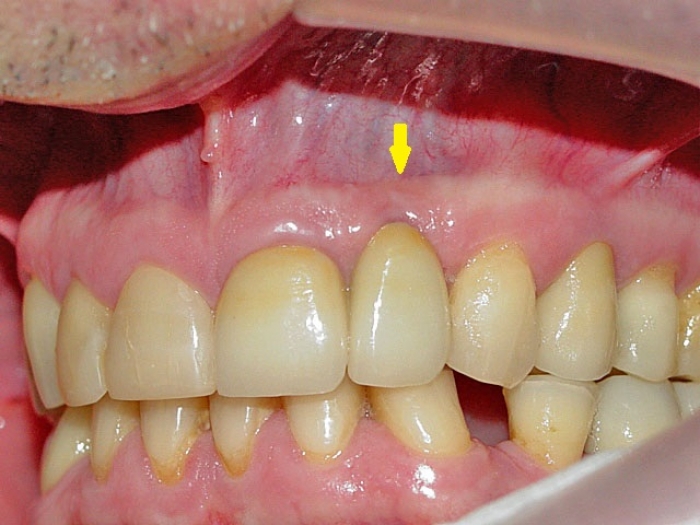

Prótese fixa em porcelana sobre implante Cone Morse

Imagem final, do caso terminado em fevereiro de 2013